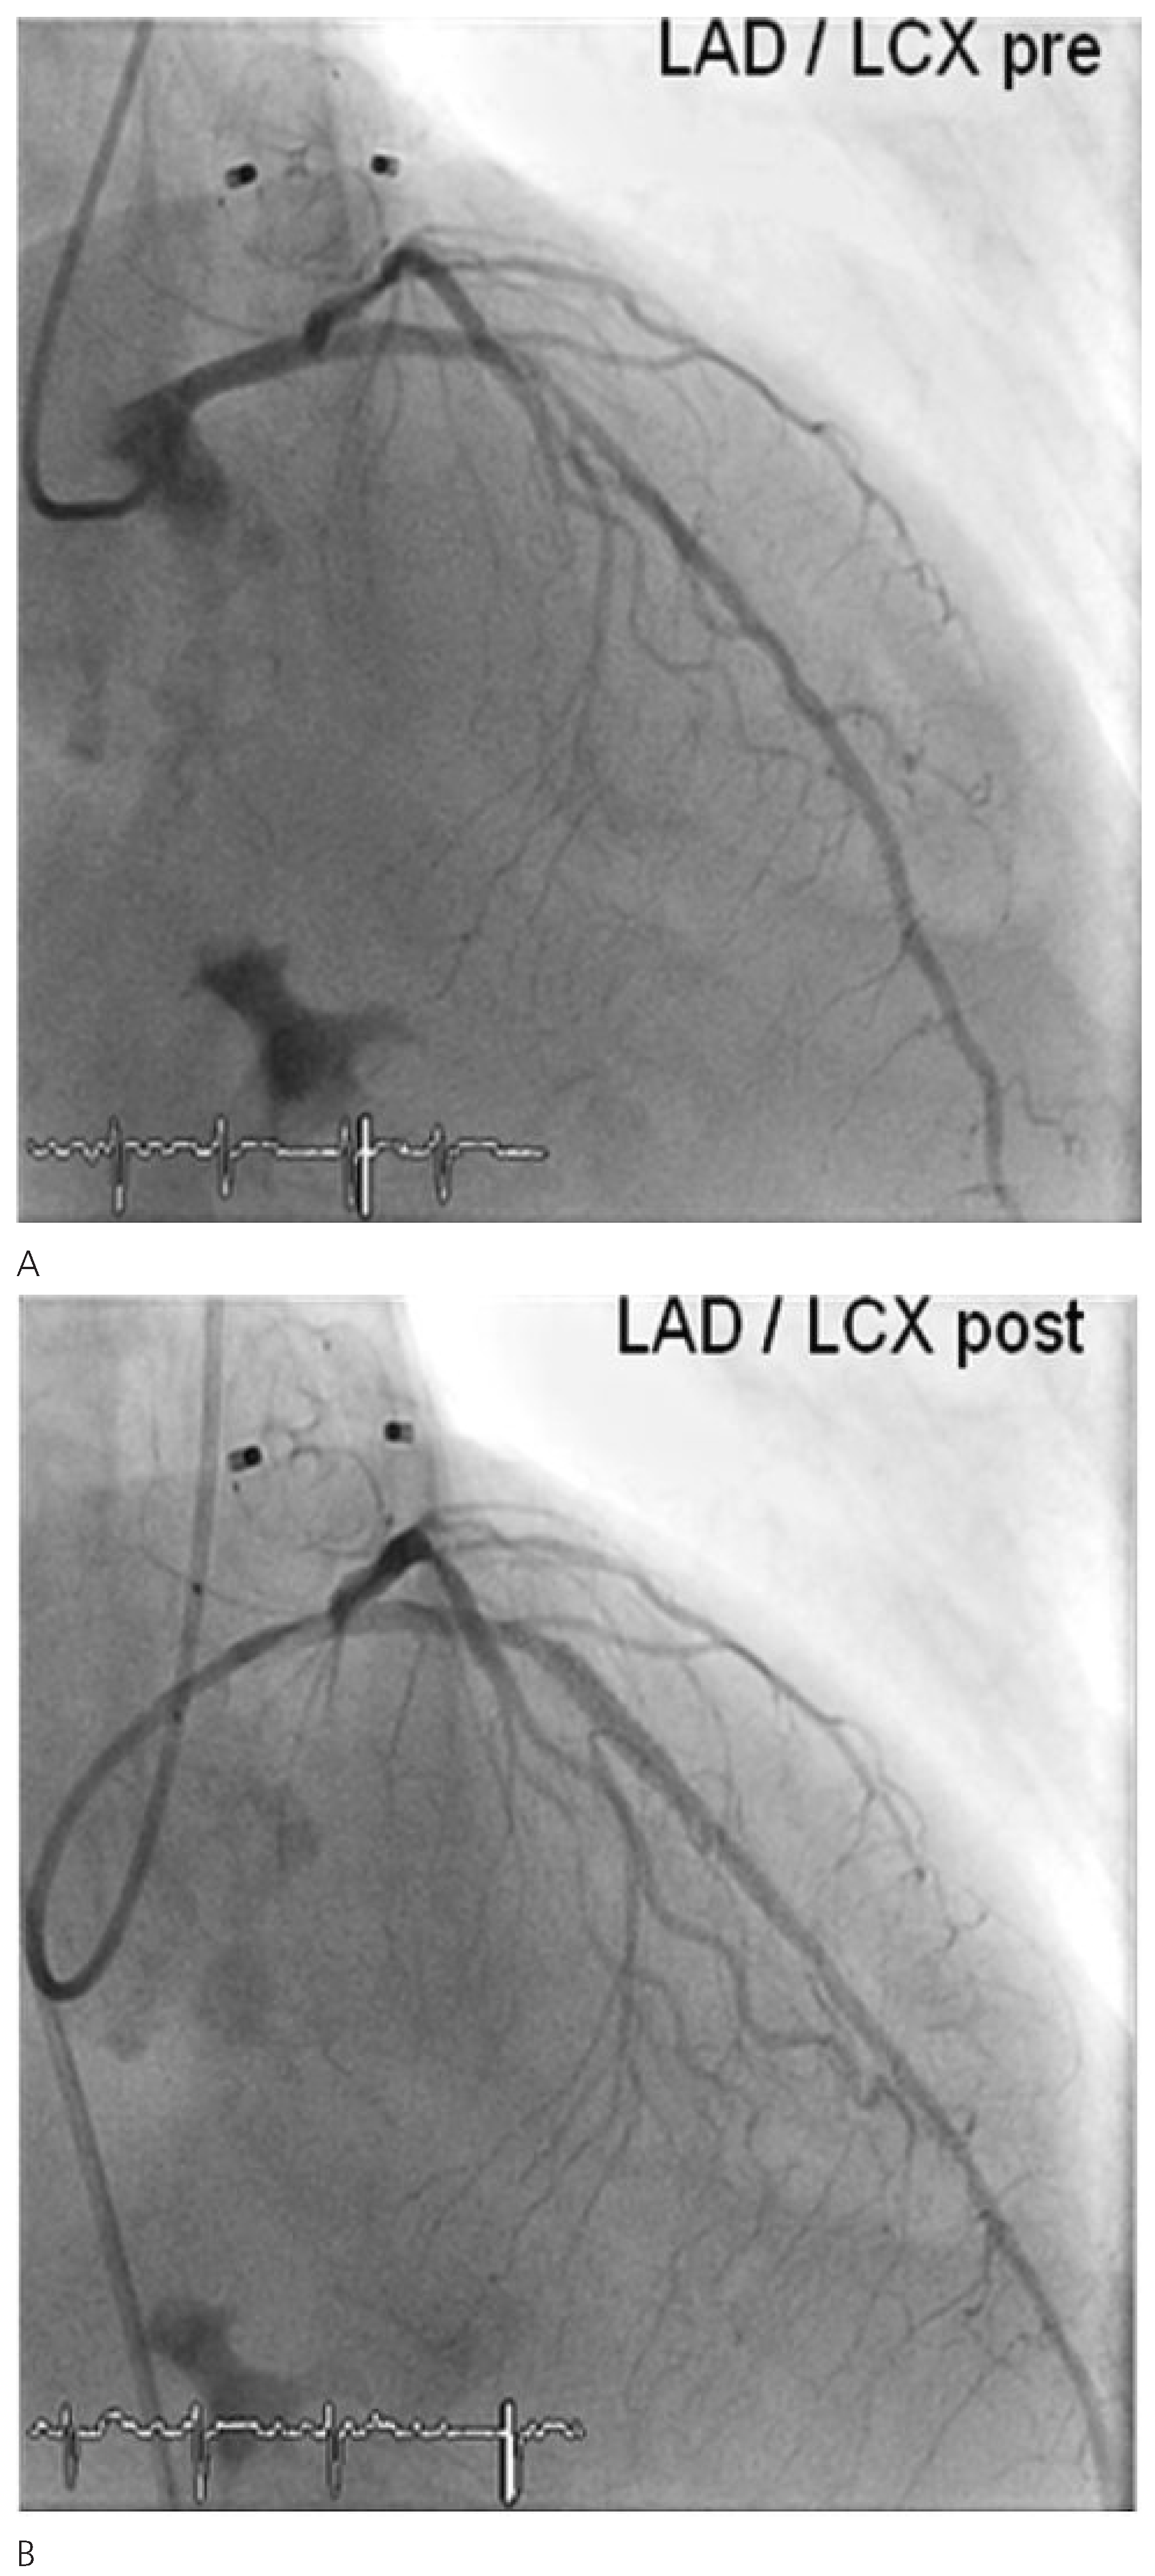

Through a transfemoral venous approach and transseptal puncture, the left atrial appendage was identified and an Amplatzer cardiac Plug 20 mm was positioned in the entry of the appendage. A stable position of the device and complete occlusion of the retroverted, single-lobulated appendage were verified by angiography before the device was released from the catheter (Figure 1 and Figure 2). Thereafter, coronary angiography was performed which showed significant stenosis of the mid left anterior descending coronary artery (LAD) and the proximal left circumflex coronary artery (LCX). Following successful treatment with two everolimus-eluting stents, respectively (Figure 3), angiography of the aorta and iliac artery was performed to measure the aortic valvar annulus and assess the peripheral access site. The patient qualified for implantation of a Medtronic CoreValve bioprosthesis and a 18 French sheath was introduced in the right femoral artery, as well as a temporary transvenous pacemaker through a right jugular access. After balloon dilatation of the degenerative aortic valve with a Nucleus balloon 25 × 40 mm under rapid pacing, the self-expandable bioprosthesis was deployed under fluoroscopic guidance (Figure 4). Periinterventional transoesophageal echocardiography demonstrated an excellent result with negligible paravalvular regurgitation. Simultaneous invasive measurement demonstrated a decrease in the mean transvalvular pressure gradient from 56 to 5 mm Hg. Closure of the right femoral access site was performed under temporary balloon occlusion of the right external iliac artery, from a contralateral femoral access with a Prostar device. The intervention was performed under general anaesthesia.

Figure 3. Percutaneous revascularisation of the mid-LAD (A) and proximal LCX (B).